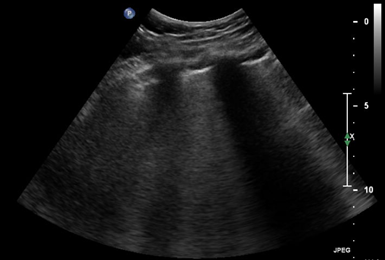

Throughout the case, the patient was managed with total doses of 0.7mg norepinephrine, 9.0mcg epinephrine, 0.4mg phenylephrine, and 23mg dobutamine while using 1L of lactated ringer to maintain adequate blood pressure. Norepinephrine has mixed alpha-1 and beta activity and was used to increase systemic vascular resistance and support myocardial contractility, leading to an increase in blood pressure and cardiac output. Epinephrine has comparable activity on alpha-1 and beta receptors and was used to increase systemic vascular resistance, heart rate, cardiac output, and blood pressure which ultimately provided additional inotropic support. Phenylephrine is an alpha-1 agonist and was given to induce peripheral arterial vasoconstriction, providing improvement in vascular tone and enhancing perfusion pressure.5 During the case, the patient continued to be hypotensive with blood pressures dropping down to 100/40mmHg and dobutamine, a beta-1 agonist with positive inotropic effects, was introduced at 19:38 to enhance cardiac output by increasing myocardial contractility.5 The thrombectomy was completed uneventfully and tolerated well by the patient (Figure 1-3).

Figure 2 Transthoracic echocardiogram (TTE) in the parasternal long-axis view at end-diastole. The left ventricle is shown to be dilated with thinned walls during diastole. The reduced difference in ventricular size between end-systole (Figure 1) and end-diastole further illustrates the decreased ejection fraction and systolic dysfunction associated with acute heart failure.